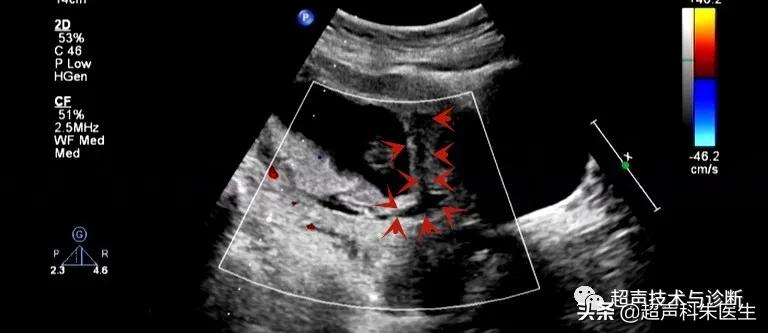

出现绒毛膜下血肿的孕妇,仅有20%会出现阴道不规则流血或下腹部疼痛的症状,而其余大多数绒毛膜下血肿是在超声检查中发现的,其超声表现为:子宫壁和胎膜(或孕囊)之间的无回声区,多位于胎盘下缘至宫颈内口间,以弧形或新月形多见,若血肿较多或血肿形成时间较长时,内可见点、絮状弱回声及条带状强回声,彩色多普勒超声检查:血肿内无血流信号。

接下来我们来看看具体病例: